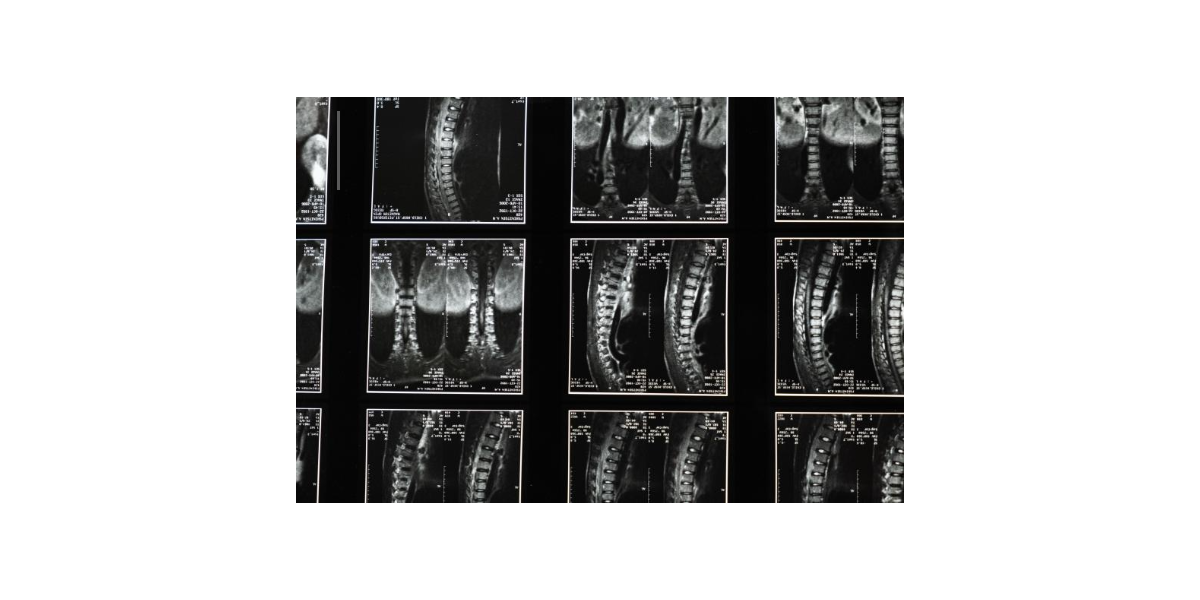

척수암의 치료는 종양의 성격, 위치, 환자의 전반적인 건강 상태에 따라 달라지며, 여러 치료법이 병행되기도 한다. 가장 기본적이면서도 근본적인 치료 방법은 수술을 통한 종양 제거다. 수술은 가능한 범위 내에서 종양을 최대한 제거하는 것을 목표로 하며, 신경 손상을 최소화하기 위해 고도의 기술과 정밀한 장비가 필요하다. 특히 척수 내부 깊숙한 부위에 위치한 종양일수록 접근이 어려워 수술 난이도가 매우 높아지며, 수술 후 회복 기간도 길어진다. 양성 종양의 경우 완전히 제거할 수 있다면 재발 가능성이 낮고, 환자의 기능 회복도 양호한 편이다. 그러나 악성 종양이거나 전이성 척수암일 경우 수술만으로는 완전한 치료가 어렵기 때문에 방사선 치료나 항암치료와 병행해야 한다. 방사선 치료는 종양의 성장 속도를 억제하고, 수술 후 남은 종양 세포를 제거하는 데 효과적이며, 통증 완화에도 도움을 준다. 최근에는 고정밀 방사선 치료 기술이 발달해 정상 조직을 최대한 보호하면서 치료 효과를 높일 수 있게 되었다. 항암치료는 일반적으로 악성 척수암에 시행되며, 전신 상태와 종양의 종류에 따라 약제와 스케줄이 달라진다. 다만 척수는 혈액-뇌 장벽이라는 구조적 보호막이 있어 약물이 도달하기 어려운 특성이 있기 때문에, 항암치료의 효과는 제한적일 수 있다. 이에 따라 신경외과, 방사선종양학, 종양내과 등 여러 분야의 전문의가 팀을 이루어 최적의 치료 계획을 수립하는 것이 중요하다. 치료 이후에는 신경 기능 회복을 위한 재활치료가 필요하다. 걷기, 균형, 근력 회복을 위한 물리치료와 함께, 통증 조절을 위한 약물 관리, 배뇨 배변 기능 개선을 위한 교육 등 다양한 접근이 병행된다. 치료가 완료되었다고 하더라도 정기적인 MRI 검사와 혈액 검사를 통해 재발 여부를 모니터링해야 하며, 특히 악성 척수암의 경우 재발률이 높아 철저한 추적관리가 필수다. 척수암은 치료 이후에도 삶의 질에 많은 영향을 미치므로, 심리적 지지 또한 매우 중요하다. 일상으로 복귀하는 데 있어 환자 스스로의 마음가짐과 가족의 지원이 큰 역할을 하며, 재활 과정에서 우울감이나 불안을 겪는 경우 전문적인 상담이 도움이 될 수 있다. 척수암은 희귀하지만 누구에게나 발생할 수 있는 가능성이 있는 만큼, 조기 발견과 꾸준한 건강 관리를 통해 예후를 개선할 수 있다는 점을 기억하는 것이 중요하다.